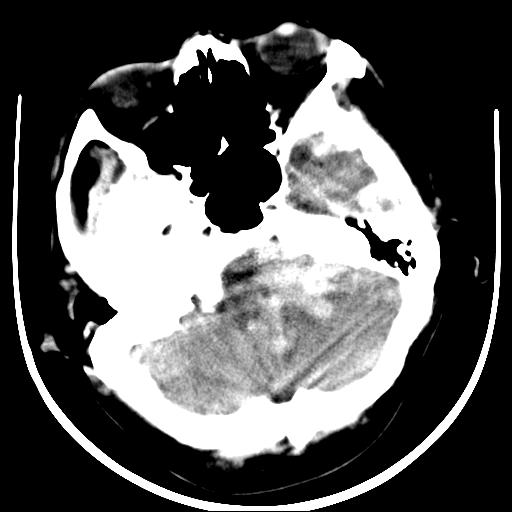

标题: CT16838:男58岁,意识不清2小时,请会诊出血部位该如何写。 [打印本页]

标题: CT16838:男58岁,意识不清2小时,请会诊出血部位该如何写。

1)脑干、左侧桥小脑臂及小脑蚓部出血破入蛛网膜下腔。2)左侧基底节区灶性出血,不排除钙化灶。3)脑室系统少量积血。4)脑积水。

(患者病情危重,出现不自主运动——是引起图像质量不佳的主要原因)